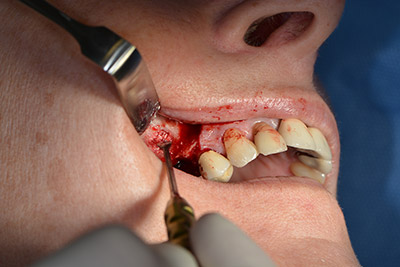

The classic incision (crestal, buccal relief) and the preparation of the mucoperiosteal flap enabled a good overview.

Sky implants (bredent) were used this case. The surgical protocol of these, specify pilot drilling at about 1200 rpm (Fig. 9).